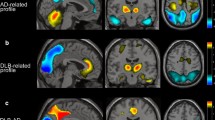

Creation of a prototype ROI map

First, stereotactic anatomical standardization was performed. The original FDG-PET image data were transformed into a binary format. They were transformed into a standard Talairach space using the NEUROSTAT program [6], which contains all three-dimensional stereotactic surface projection (3D-SSP) programs (Dr. Minoshima, Department of Radiology and Bioengineering, University of Washington, Seattle, USA). Differences in size between the individual brain and the standard template were removed by linear scaling. Regional anatomical differences between the individual and the standard template were minimized by automated non-linear warping. Next, peak cortical activity in the brain was subjected to a three-dimensional search with a predefined vector for each stereotactic surface pixel after anatomical standardization. The peak value was projected back and assigned to the originating surface pixel. This procedure was continued on a pixel-by-pixel basis covering the whole cortex of the brain. Pixel values of an individual’s image set were normalized to the whole brain, the thalamus, the pons, the cerebellum and the sensorimotor value with the 3D-SSP program in NEUROSTAT [6]. The sensorimotor cortices were defined as reference regions for normalization [9, 10]. Pixels with significantly decreased metabolism in the DLB group (p < 0.05), which were obtained from a comparison between the AD group and the DLB group (the first group), were plotted as a prototype DLB ROI map (Fig. 1). The AD group had no regions with significantly lower metabolism compared with the DLB group (the first group).

For each individual surface projection image, a Z score was calculated for each pixel—Z score=([normal mean]−[individual value])/(normal SD)—using a normal database produced in the previous study [5], and the scores were shown as a Z score map. The averaged Z scores in each area of the prototype DLB ROI map were calculated. Two threshold values were tested, mean+2SD and mean+3SD, these values being derived from the AD patients in the first group. The mean and SD and threshold values in each region of the first group are shown in Table 2.

In the same way, the Z score images of the second group were obtained and the averaged Z scores were also calculated with the ROI map. We diagnosed as DLB any subject with more than one area in the bilateral medial and lateral occipital lobes where averaged Z scores exceeded the thresholds for DLB in this system.

The averaged Z scores in each area of the ROI map obtained in the second group are shown in Table 3. All the averaged Z scores in each region for DLB were significantly larger than those for AD. The fully automatic diagnosis system demonstrated an accuracy of 73%, a sensitivity of 75% and a specificity of 72% for the mild DLB group when the threshold was set at the mean+2SD. When using the threshold of the mean+3SD, an accuracy of 61%, a sensitivity of 38% and a specificity of 76% were demonstrated.

Representative cases

Figure 3 shows the conventional FDG-PET images (a) and Z score map (b) of a 74-year-old male patient with DLB. His MMSE score was 26. All the observers could easily diagnose this case as DLB by visual inspection of the conventional FDG-PET images because of a typical metabolic reduction pattern. The automatic diagnosis system also diagnosed it as DLB. Figure 4 shows the conventional FDG-PET images (a) and Z score map (b) of a 71-year-old female with AD. All the observers and the automatic system could diagnose this case as AD. Figure 5 shows the findings in a 74-year-old male DLB patient with an MMSE score of 21; two experts and one beginner diagnosed this case as DLB, while the other expert considered it equivocal and the other beginner diagnosed it as AD. The automatic diagnosis system could not diagnose this case as DLB.

Diagnostic imaging methods, such as MRI or nuclear medicine methods, are helpful in diagnosing DLB accurately. The revised consortium proposed that imaging investigation can also be helpful in supporting a diagnosis [4]. In DLB, the volume of the hippocampal and the medial temporal lobe is preserved and atrophy of the putamen is demonstrated by MRI volumetry. However, it is not easy to demonstrate the morphological difference between mild DLB and mild AD. Occipital hypoperfusion on single-photon emission computed tomography (SPECT) and hypometabolism on PET have been shown without occipital lobe atrophy on MRI [16–19]. The metabolism and perfusion of the medial and lateral occipital lobe are characteristically affected in DLB, and these are the features that discriminate it from AD [20]. Dopaminergic and cholinergic impairment is considered to be the cause of the hypometabolism and hypoperfusion in the occipital lobe [3, 16, 21, 22]. In this study we tried to diagnose mild DLB with occipital hypometabolism using FDG-PET and 3D-SSP automatically. We used the NEUROSTAT program for 3D-SSP, which is able to transform atrophied brain to standard brain more correctly than the statistical parametric mapping (SPM) method [23] and to compensate for inappropriate anatomical standardization [6]. An important step in this statistical method was the selection of the reference area for the normalization: we chose the sensorimotor area for this system because of the relative preservation of metabolism in the sensorimotor cortex in DLB patients [10]. The fully automatic diagnosis system for differentiation of mild DLB from mild AD was able to perform at a similar diagnostic level to visual inspection of conventional axial FDG-PET images by expert readers.